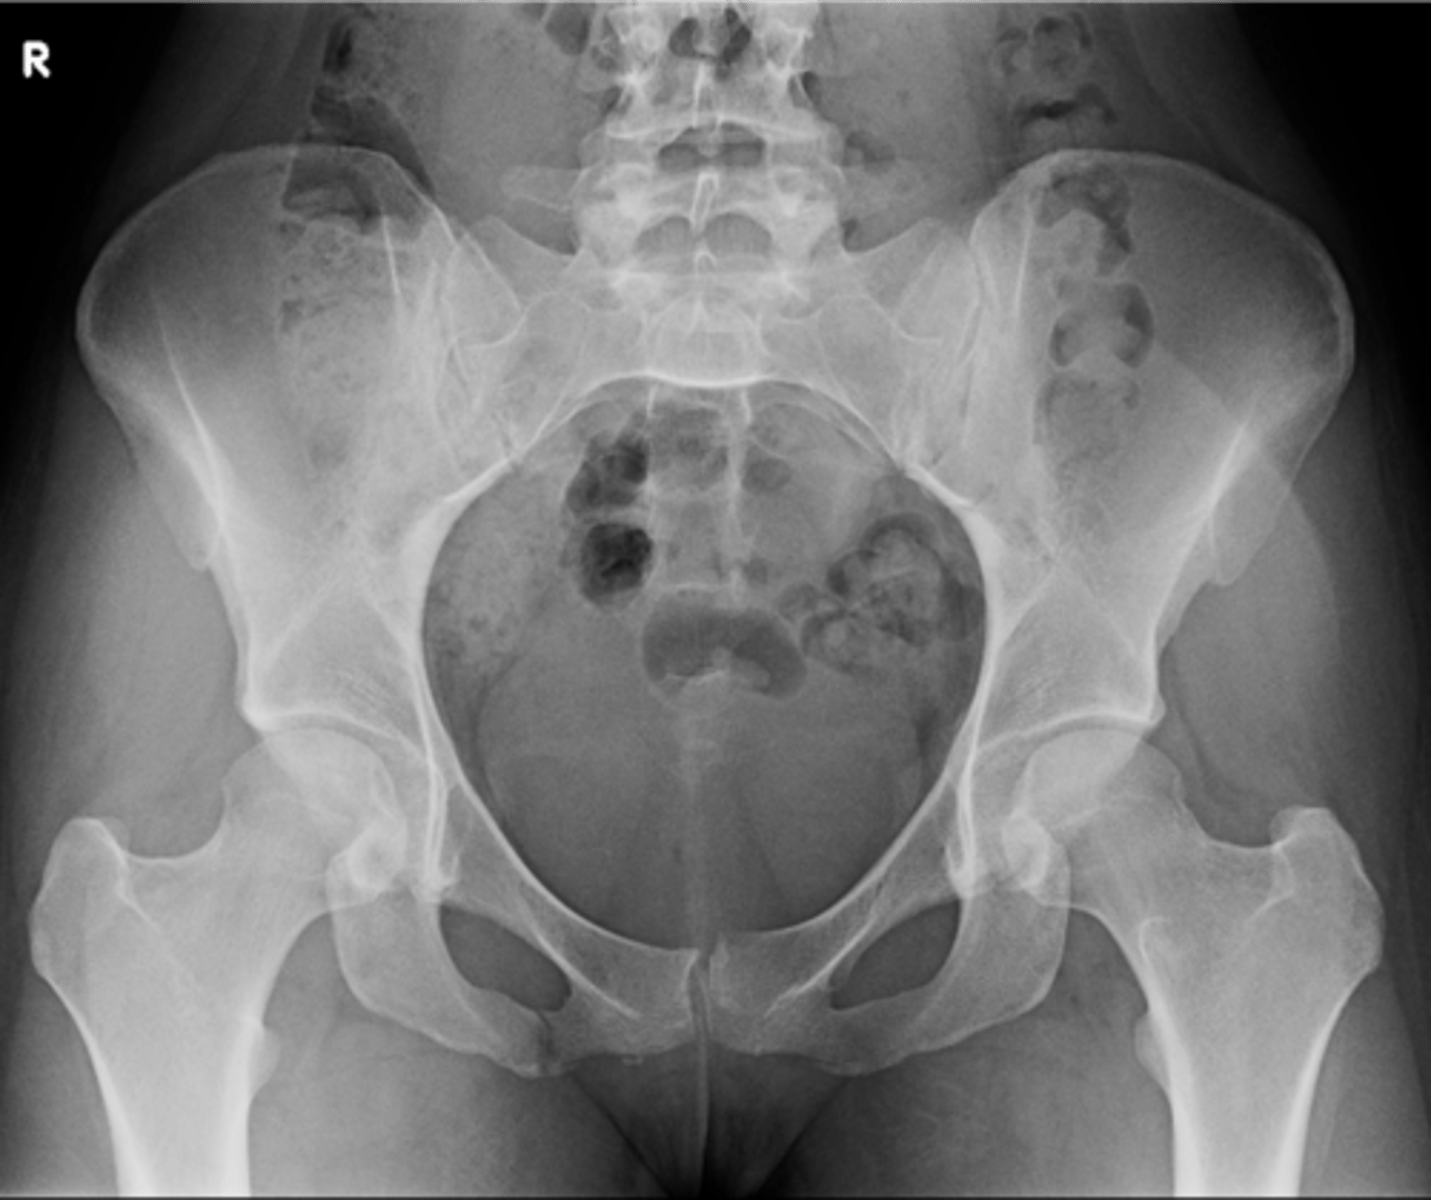

1

New cards

AP pelvis

View?

<p>View?</p>

2

Right lesser trochanter

ID 2

<p>ID 2</p>

3

Left greater trochanter

ID 3

<p>ID 3</p>

4

Right iliac crest

ID 4

<p>ID 4</p>

5

Right iliac fossa

ID 5

<p>ID 5</p>